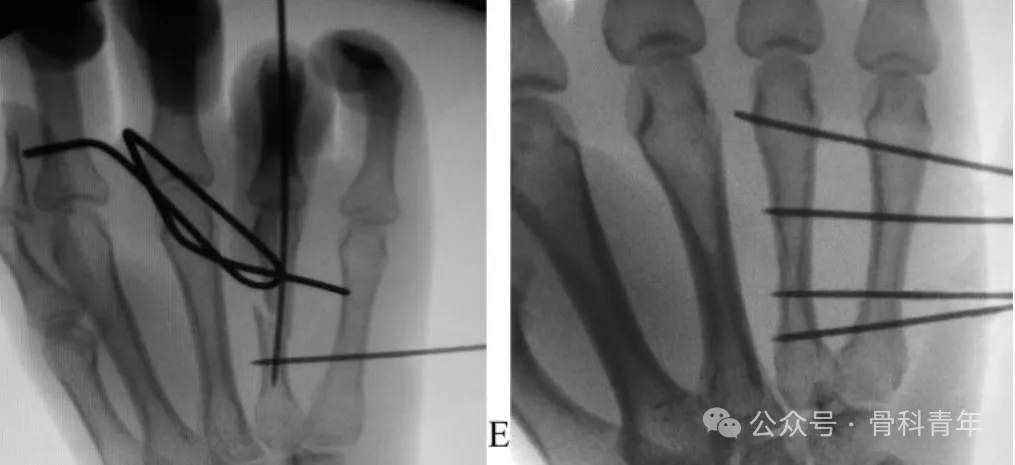

步骤2:掌指关节屈曲90°,经掌骨远端关节面置入一枚1.5mm克氏针,穿入远端骨块髓内。后牵引环指、挤压骨折断端闭合复位,如复位困难,可采用克氏针经皮撬拨或将克氏针折弯后辅助复位(如下图)。

步骤3:复位后,将远端髓内克氏针直接穿入近端骨块髓腔,临时维持复位。在位置满意后,经第5掌骨置入2枚克氏针至远端骨块,再置入一枚固定近端。在远近端各固定2枚后,去除髓内固定克氏针。固定后克氏针留置皮外,可回归工作。